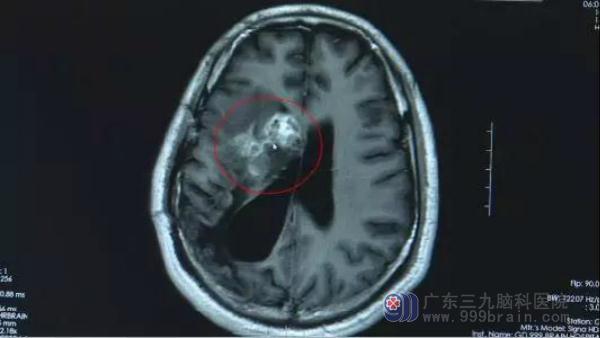

然而寄生虫位于脑部功能区

医生不敢贸然手术

因为稍有不慎就会引起瘫痪

一条长约12厘米的裂头蚴

被顺利“擒住”了